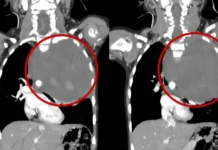

Длительное время Белле приходилось справляться с неприятными ощущениями самой, пока осенью 2019 года ее состояние не ухудшилось настолько, что потребовалась повторная госпитализация. В этот раз врачи не ограничились поверхностным осмотром и направили ее на эндоскопию. Исследование выявило в желудке Беллы шестисантиметровую стромальную опухоль — редкий тип образования, требующий незамедлительного вмешательства.

Из-за того, что болезнь долго оставалась без внимания, опухоль успела значительно вырасти. Врачи были вынуждены удалить 70% желудка, чтобы остановить дальнейшее развитие заболевания и дать Белле шанс на полноценную жизнь.